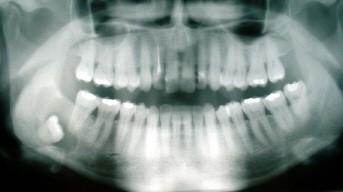

Which type of anatomic structure are wisdom teeth?

Wisdom teeth are the third and final set of human molars that come in during the late teens or early twenties. In some cases, these teeth come in without problems, but they often have to be removed due to misalignment in the jaw, as shown below. Removal of the teeth does not cause any long-term complications in regard to eating.

Vestigial